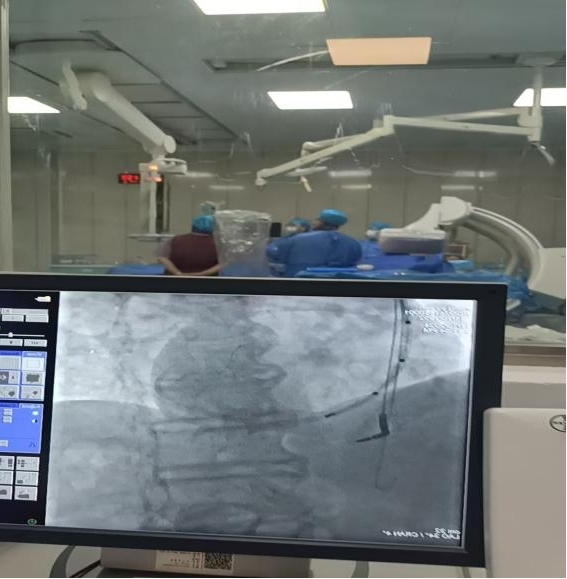

今年11月10日,我院心血管二病區(qū)成功植入第一例心臟CRT-D。72歲的張先生因心臟衰竭入院,入院后心電圖提示完全性左束支傳導(dǎo)阻滯,心臟彩超提示左心增大,心功能不全。張先生入院時(shí)通過藥物緩解癥狀后行冠脈造影檢查,結(jié)果提示冠脈中度狹窄,排除冠脈缺血引起的心臟衰竭,考慮擴(kuò)張型心肌病。心電圖及動(dòng)態(tài)心電圖提示完全性左束支傳導(dǎo)阻滯,頻發(fā)室性早搏,表示心臟左右心室收縮嚴(yán)重不協(xié)調(diào),同時(shí)這類患者有潛在惡性室性心律失常風(fēng)險(xiǎn),從而進(jìn)一步加重心衰或猝死的風(fēng)險(xiǎn)。張先生植入CRT-D后心衰癥狀明顯緩解,且室性早搏較前明顯減少。心臟收縮功能得到初步改善,術(shù)后一周,切口愈合良好。11月17日,張先生安全出院。